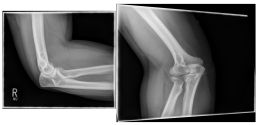

Ellenbogen

Photo: An undislocated fracture that can be treated conservatively.